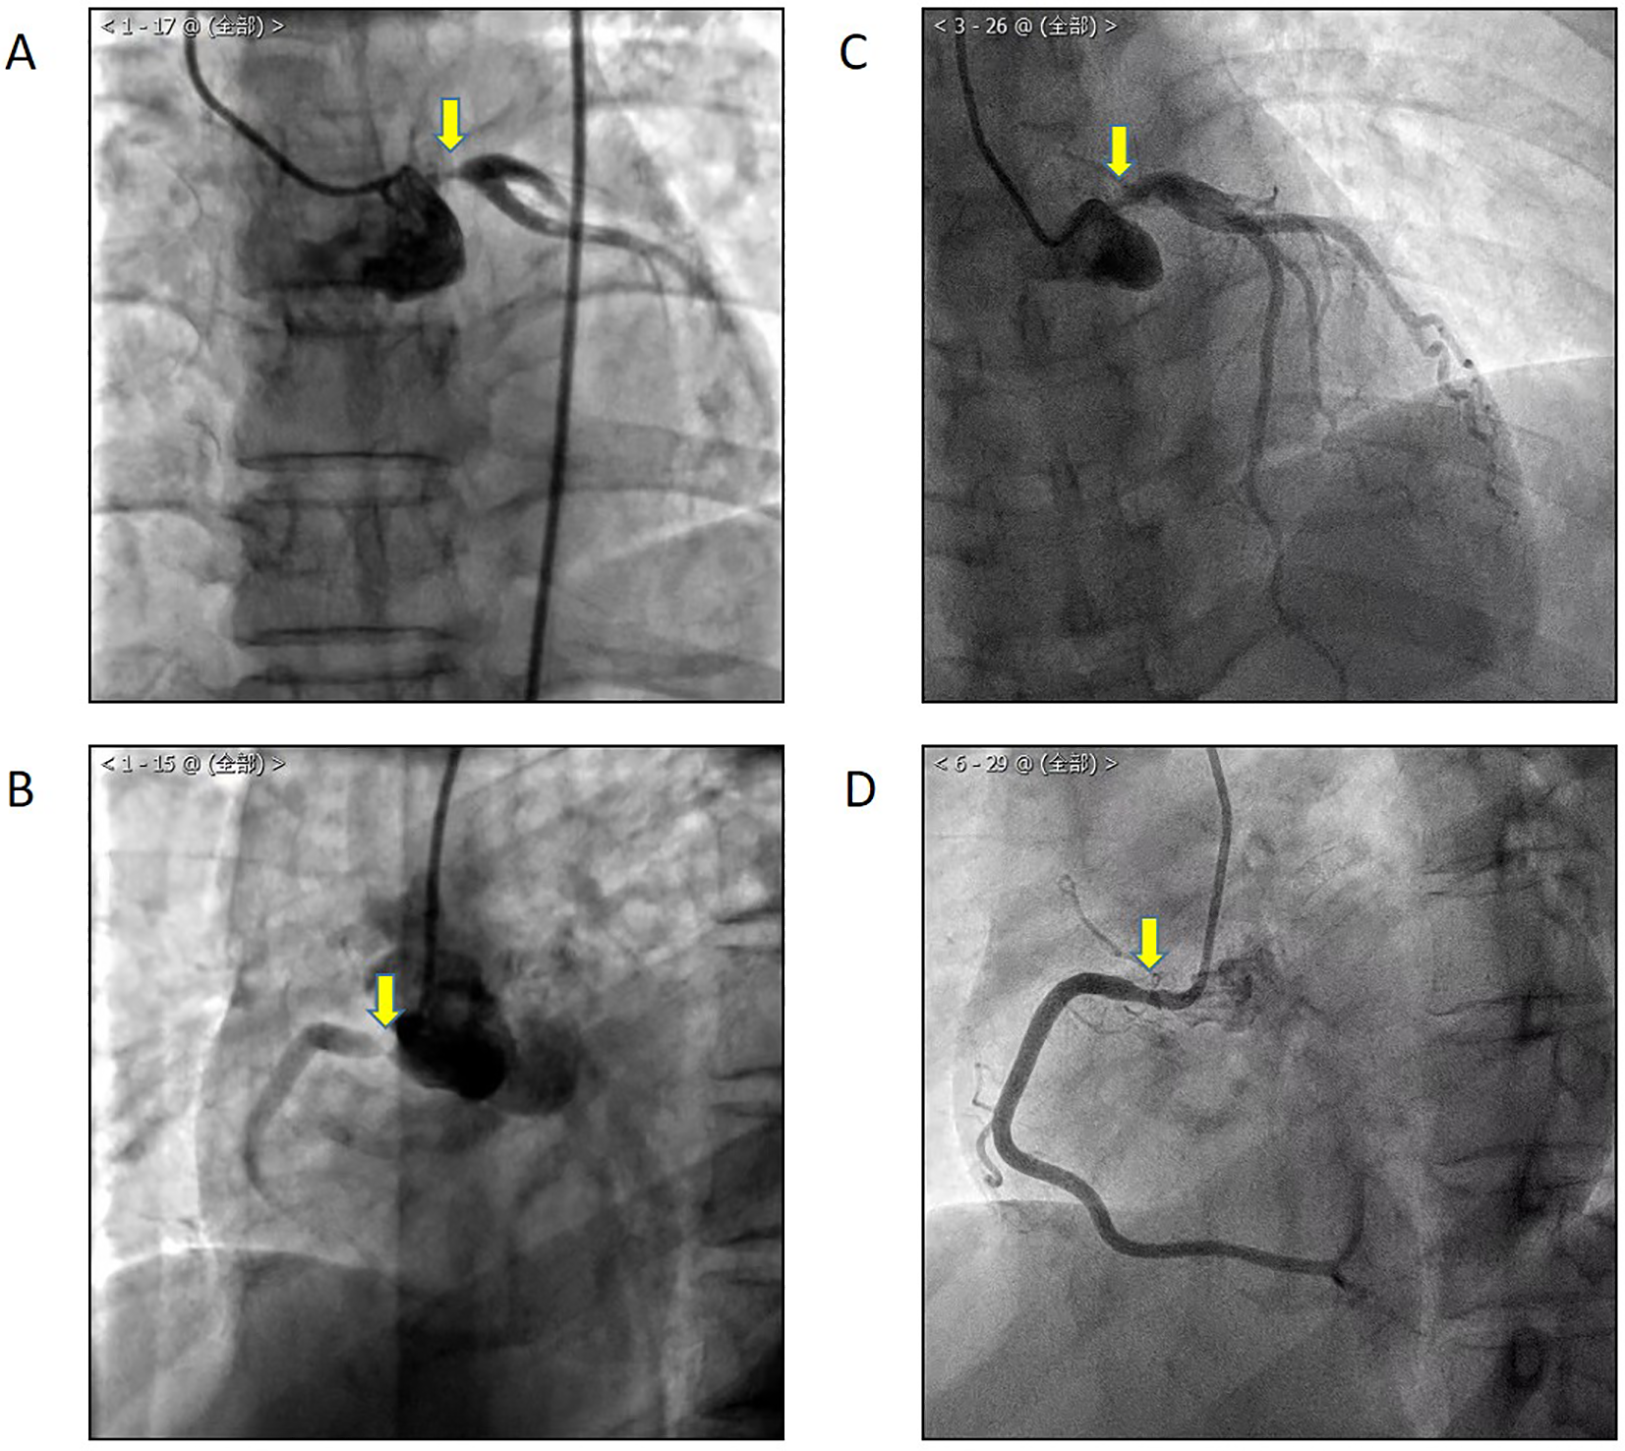

A 49-year-old female patient was admitted in 2021 with a complaint of chest tightness and a shortness of breath, symptoms that had been present for a year and were exacerbated by satiety and physical activity. She was diagnosed with non-ST segment elevation myocardial infarction with stenosis of the left main trunk (LM) and right coronary artery (RCA) (Figure 1) and had undergone percutaneous trans-luminal coronary angioplasty and intervention, followed by secondary prevention and treatment for coronary heart disease. Recently, the aforementioned symptoms have re-emerged. The patient reported no fever, rash, oral or genital ulcers, erythema nodosum, or intermittent claudication.

In 2020, CAG showed LM (A) and RCA (B) stenosis. One year after percutaneous coronary intervention, the patient suffered from chest tightness and a shortness of breath again, and CAG showed LM (C) and RCA (D) in-stent restenosis.

Upon review, coronary angiography (CAG) showed in-stent restenosis (Figure 1). Echocardiography revealed thinning of the left ventricular inferior wall basal segment, mild aortic regurgitation, and decreased left ventricular diastolic function. Positron emission tomography/computed tomography (PET/CT) demonstrated an increased uptake of (18)F-fluorodeoxyglucose (18F-FDG) in the aorta and its primary branches, as well as in the coronary arteries (Figure 3).